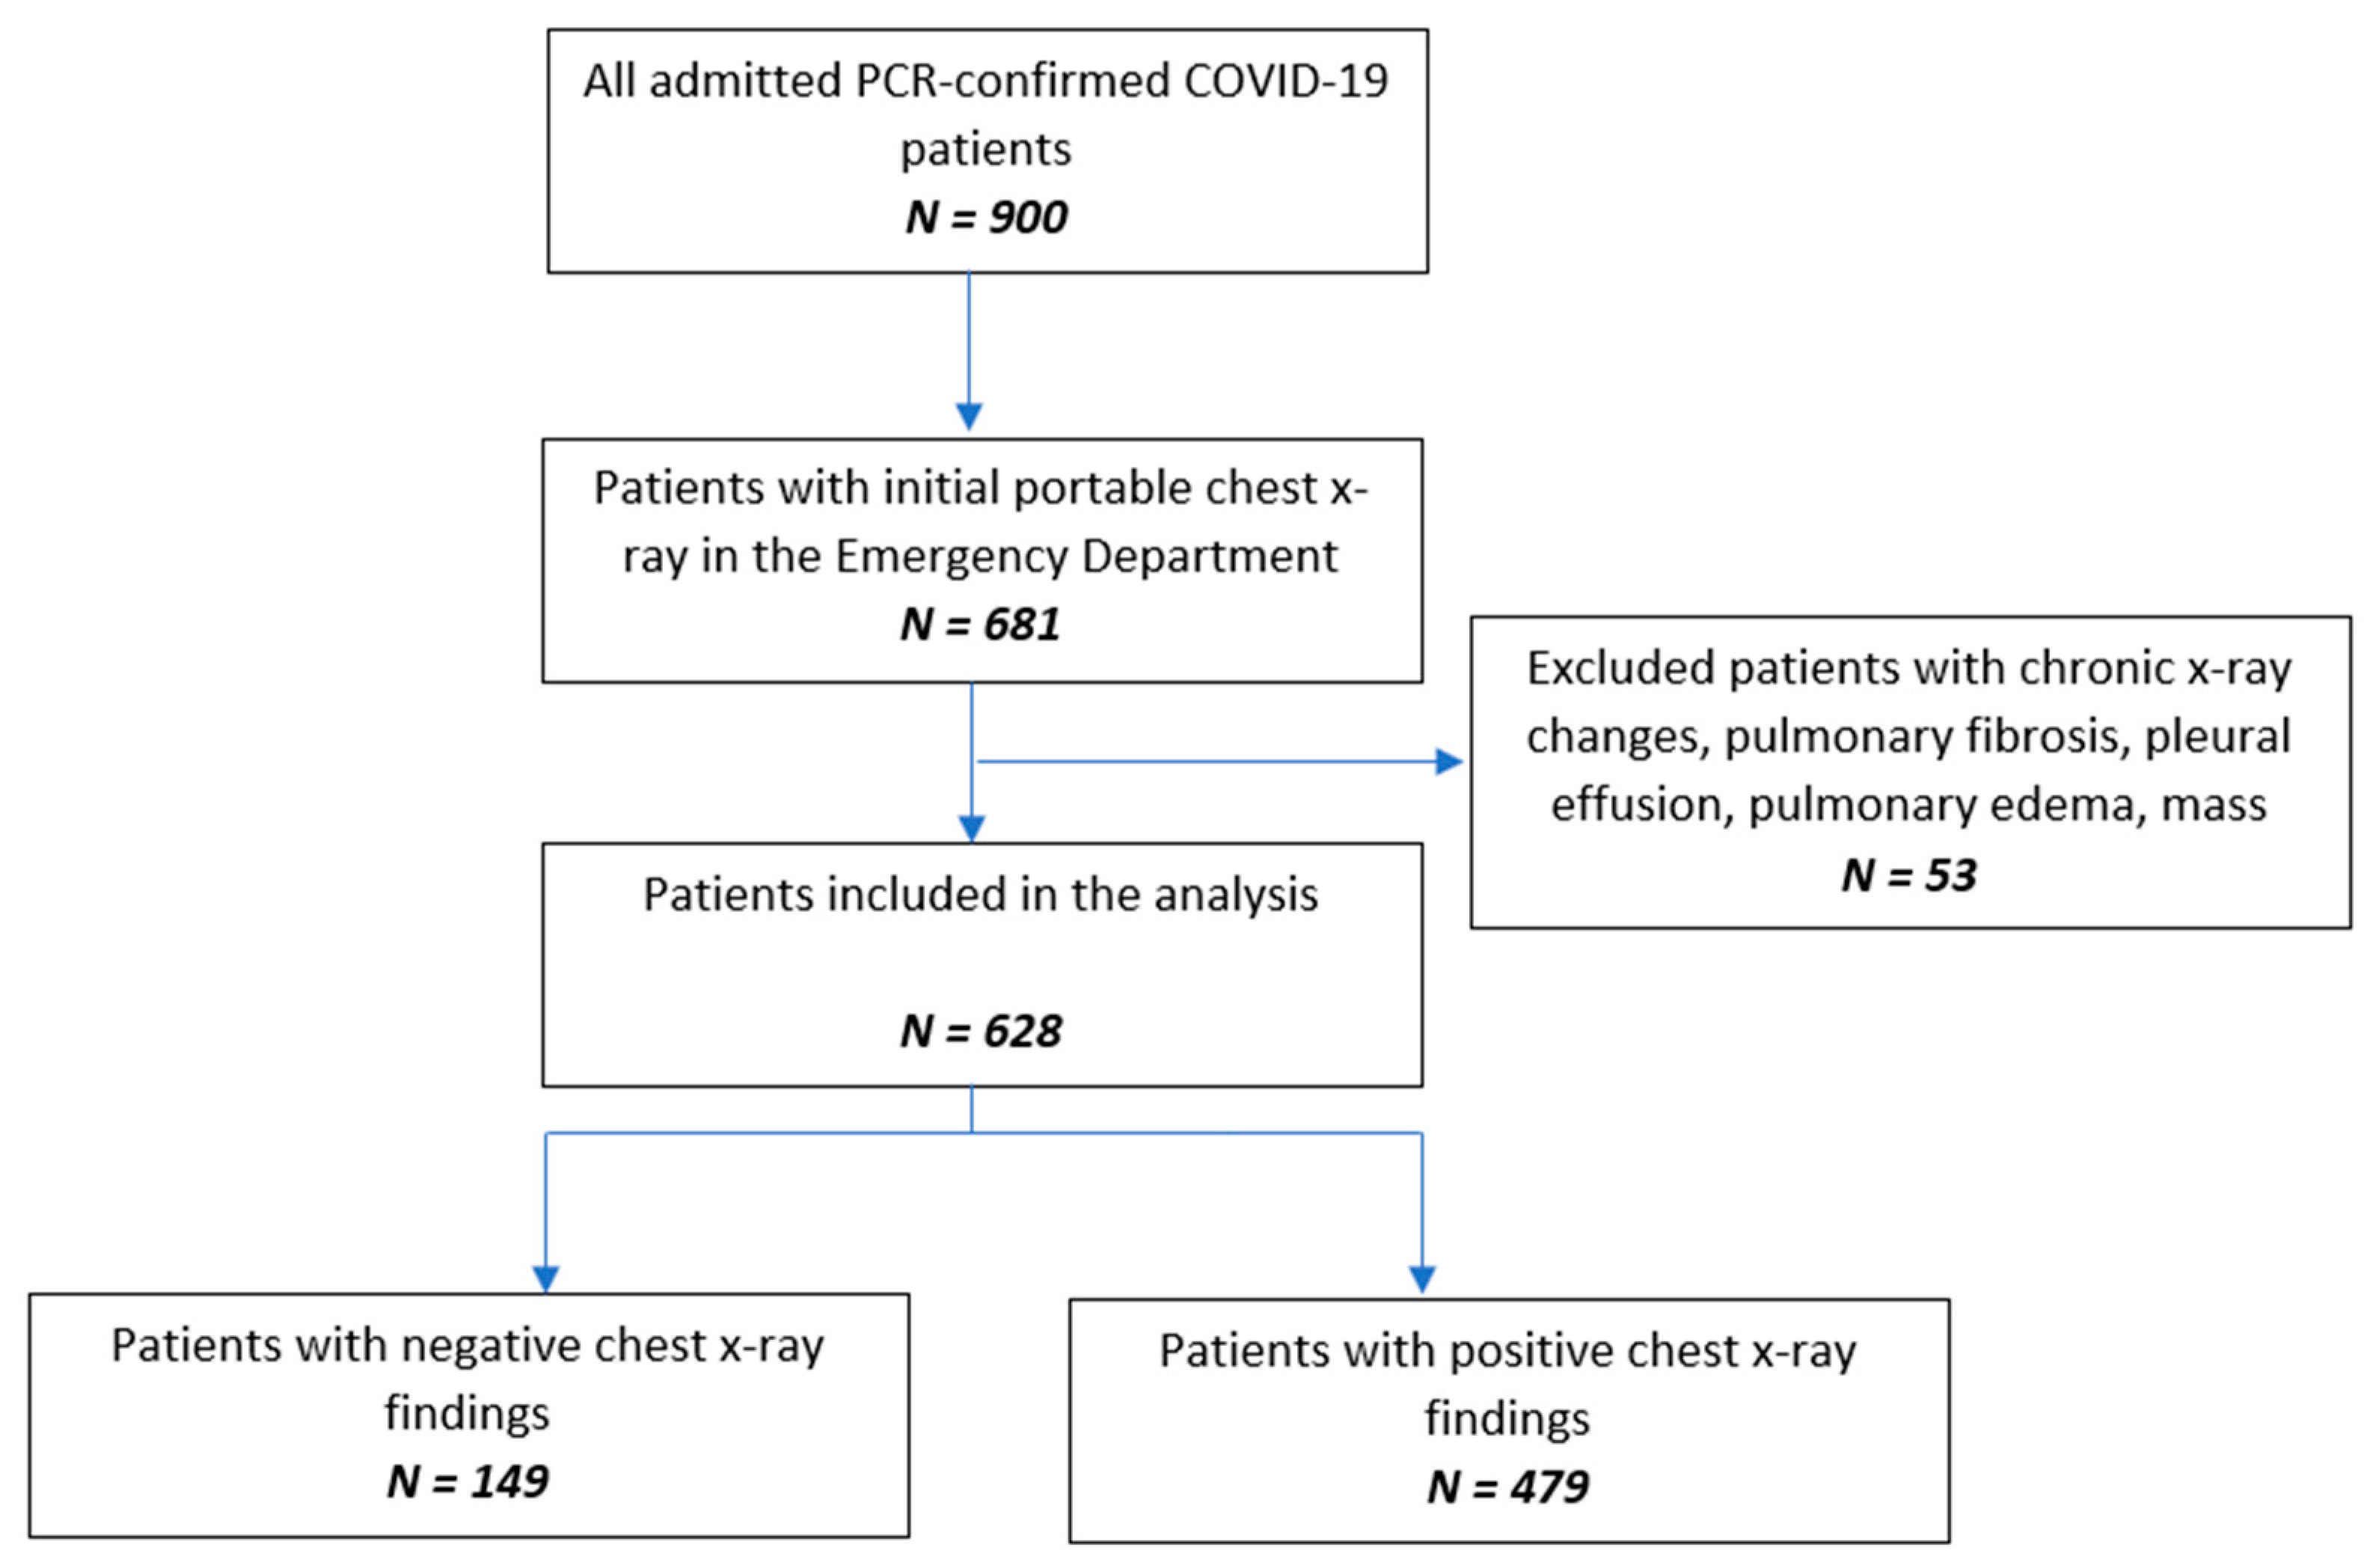

2.1. Study Design and Sample Population

2.3. Imaging and Analysis